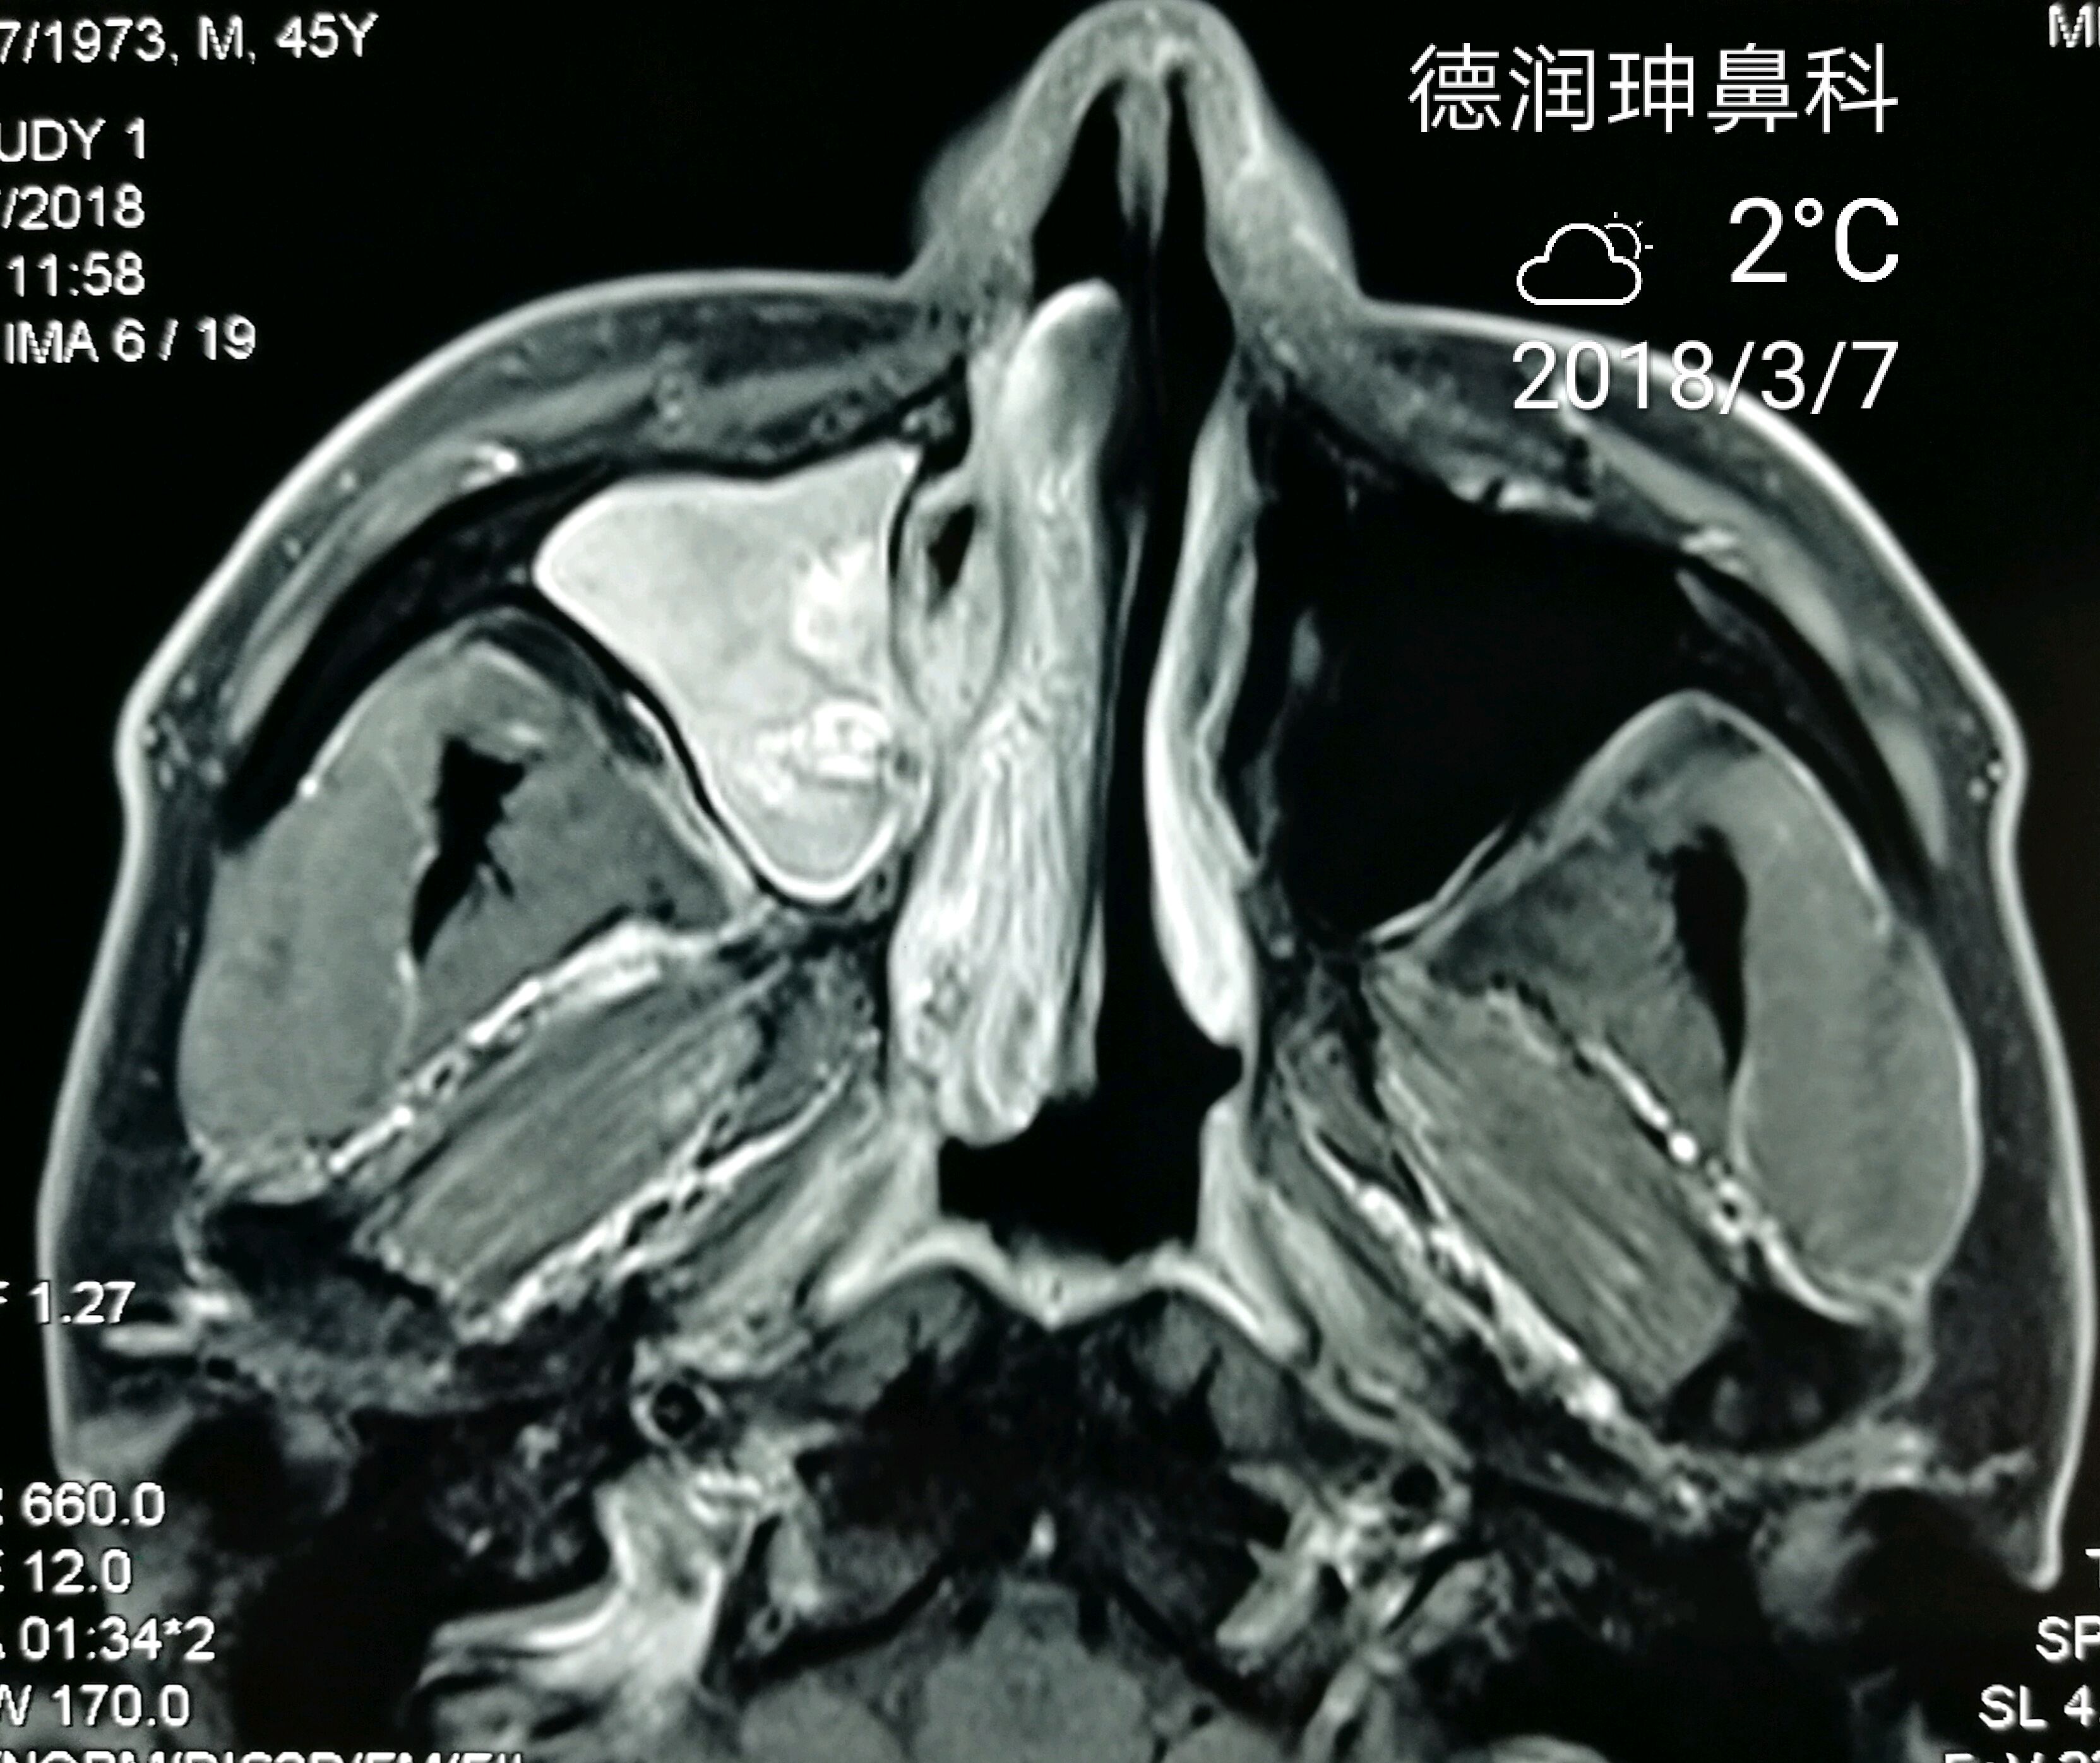

内翻性乳头状瘤一例

图片尺寸2204x1652